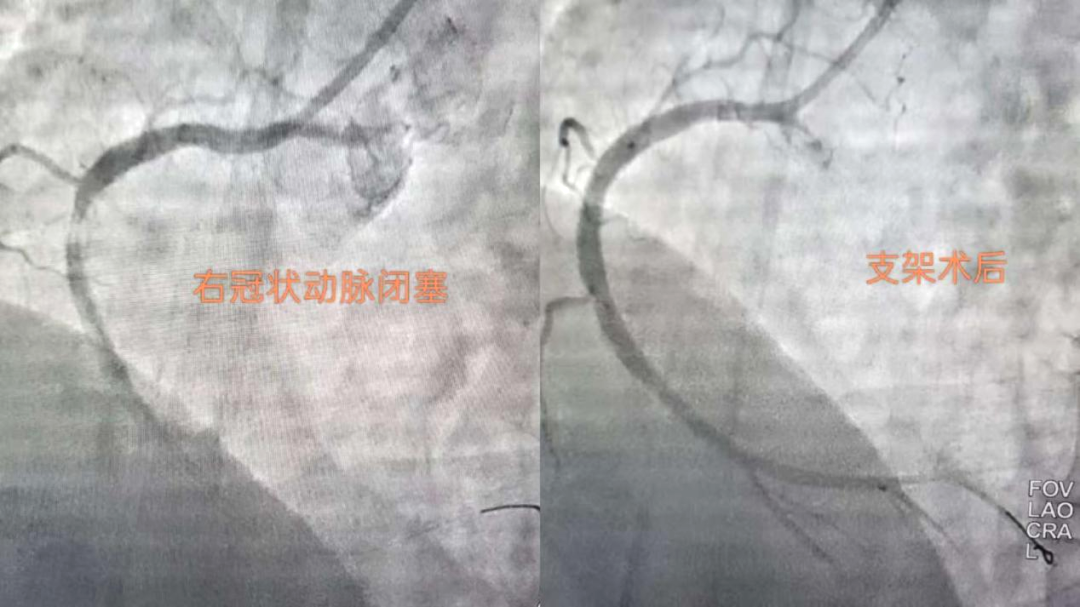

搶時(shí)間就是搶生命!06:46穿刺,06:47成功,06:49冠脈造影明確:右冠狀動(dòng)脈中段完全閉塞。導(dǎo)絲迅速通過(guò),支架精準(zhǔn)植入,07:03血流恢復(fù),手術(shù)成功結(jié)束?;颊咝赝疵黠@緩解,生命體征趨于平穩(wěn)。從入院到血管再通,不到兩小時(shí)。